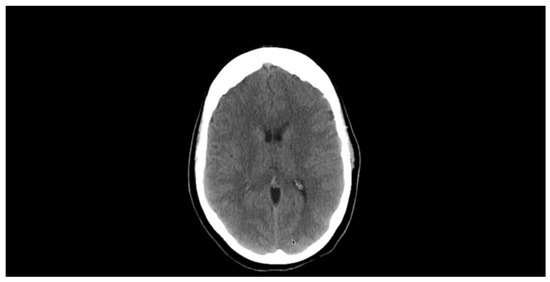

A repeat brain CT with contrast was performed 3 months after discharge from the hospital, and it showed complete resolution of the lesions Figure 4. There was also no further recurrence of the symptoms at the 1-year follow-up visit, and no neurological abnormality was noted during clinical examination of the patient. The patient was able to detect light sources and images following the experimental treatments, but still was unable to describe images that he sees, thus partial bilateral blindness was evident.

Figure 4.

Brain CT showing complete resolution of scolexes following three-month albendazole therapy.